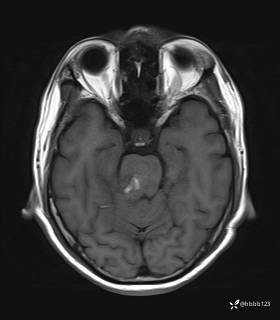

患者男,51岁。

简要病史:患者自述于1周前至某人民医院发现脑干肿瘤(具体不详),为求进一步诊断至我院就诊。

完善颅脑MRI平扫+增强,颅脑CT平扫:

T1: